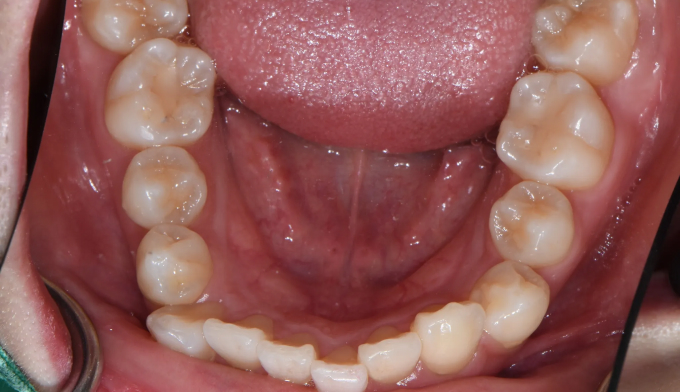

Before